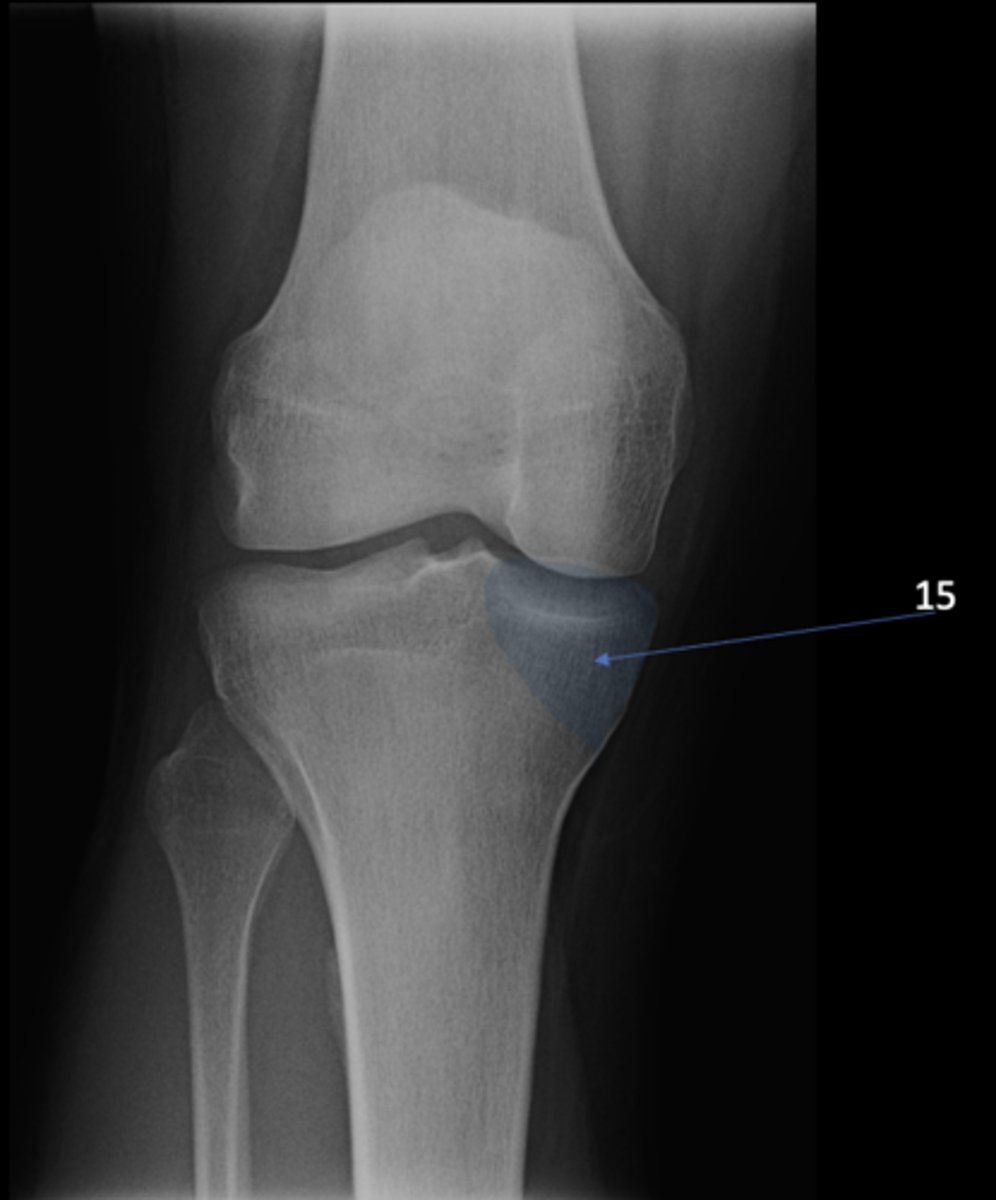

AP knee

View?

<p>View?</p>

63

New cards

Medial tibial condyle

ID 15

<p>ID 15</p>